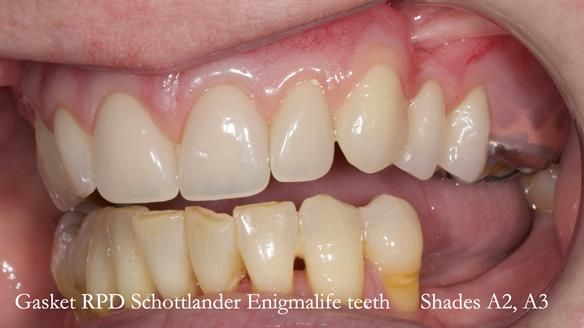

Welcome to my Newsletter 58, where I show the making and fitting of an upper gasket partial denture for Zoe (52 year old woman). This issue provides a comprehensive overview of the entire protocol workflow for this superbly retained denture.

Zoe was referred to me for specialist prosthodontics by her general dentist, after unsuccessful attempts to provide a denture because of fractures, looseness and discomfort.

The current denture could be enhanced both in terms of fit and aesthetics.

The detailed clinical situation and treatment process are outlined below, with clinical work provided by me and technical work by Rowan Garstang. The treatment spanned five visits for denture fitting and one review.